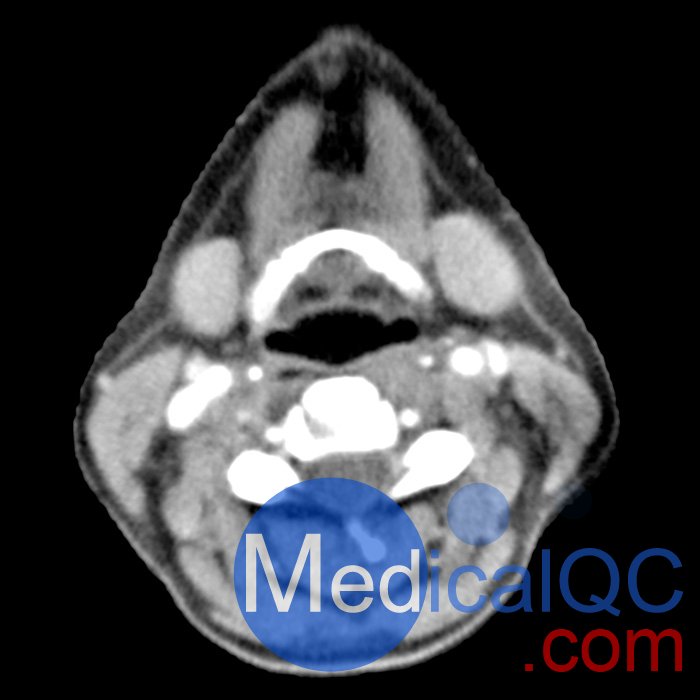

phantomX頭部模體具有逼真解剖結構的頭頸部模體

頭頸部體模提供逼真的解剖結構,旨在模擬計算機斷層掃描、X 射線成像和放射治療中的臨床成像。這些模型在定義的能譜下提供了所有組織的真實模擬和真實的衰減值。

phantomX頭頸部模型,phantomX頭部模體是根據 CT 數據制造的,包括所有組織的解剖細節。它經過優化,可在計算機斷層掃描中以 120 kVp 成像提供真實的衰減值,對應于 73 keV 的平均光譜能量。可根據要求校準其他光譜能量。

體模的尺寸和設計可能會發生細微變化。體模可以作為一件式擬人體模或以截面設計的形式提供。可以包括病理特征(例如,腫塊、血管病變)。